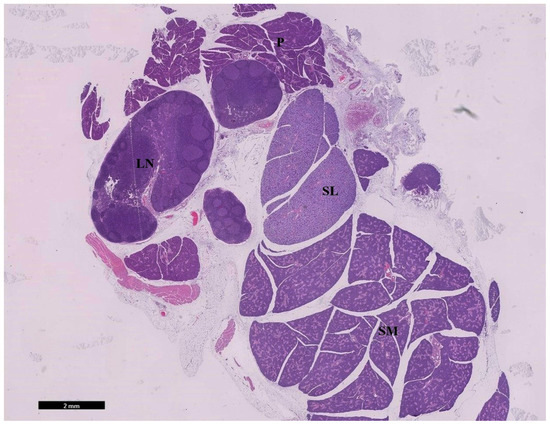

3.1.1. Examination of Hematoxylin and Eosin-Stained Sections